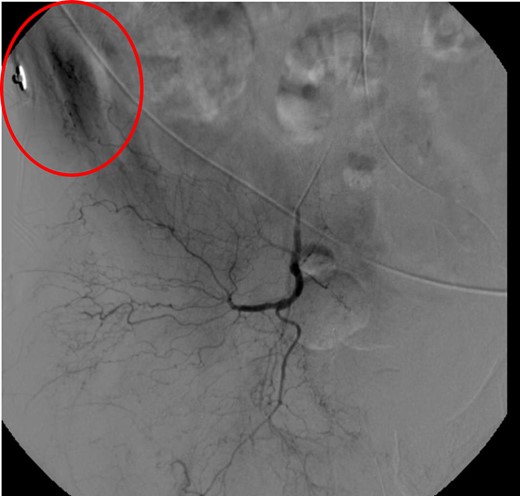

CT abdomen/pelvis with contrast was performed and a blush of contrast was noted posterior to the right pubic bone. Prior to taking patient for exploratory surgery, he was transferred to the interventional radiology suite where a pelvic angiogram was performed revealing an abnormal blush localized to the distal branches of the right iliolumbar artery (Fig. 2). Delayed phase of the angiogram demonstrated early venous filling consistent with a traumatic arteriovenous fistula which was embolized with 300–500 µ of embospheres and three 3 × 2 microcoils (Figs 3 and 4).

CT angiogram demonstrating successful embolization of AV fistula.

After resolution of the traumatic arteriovenous fistula (Fig. 2), a second blush from the right distal internal pudendal artery was identified and successfully treated with Gelfoam slurry. Subsequently, patient underwent exploratory laparotomy which revealed mesenteric and retroperitoneal hematomas. He also underwent craniotomy for evacuation of the subdural hematoma and open reduction internal fixation of the anterior and posterior pelvis. After discharge in fair condition to a subacute rehabilitation facility, patient developed a deep venous thrombosis managed by Coumadin.